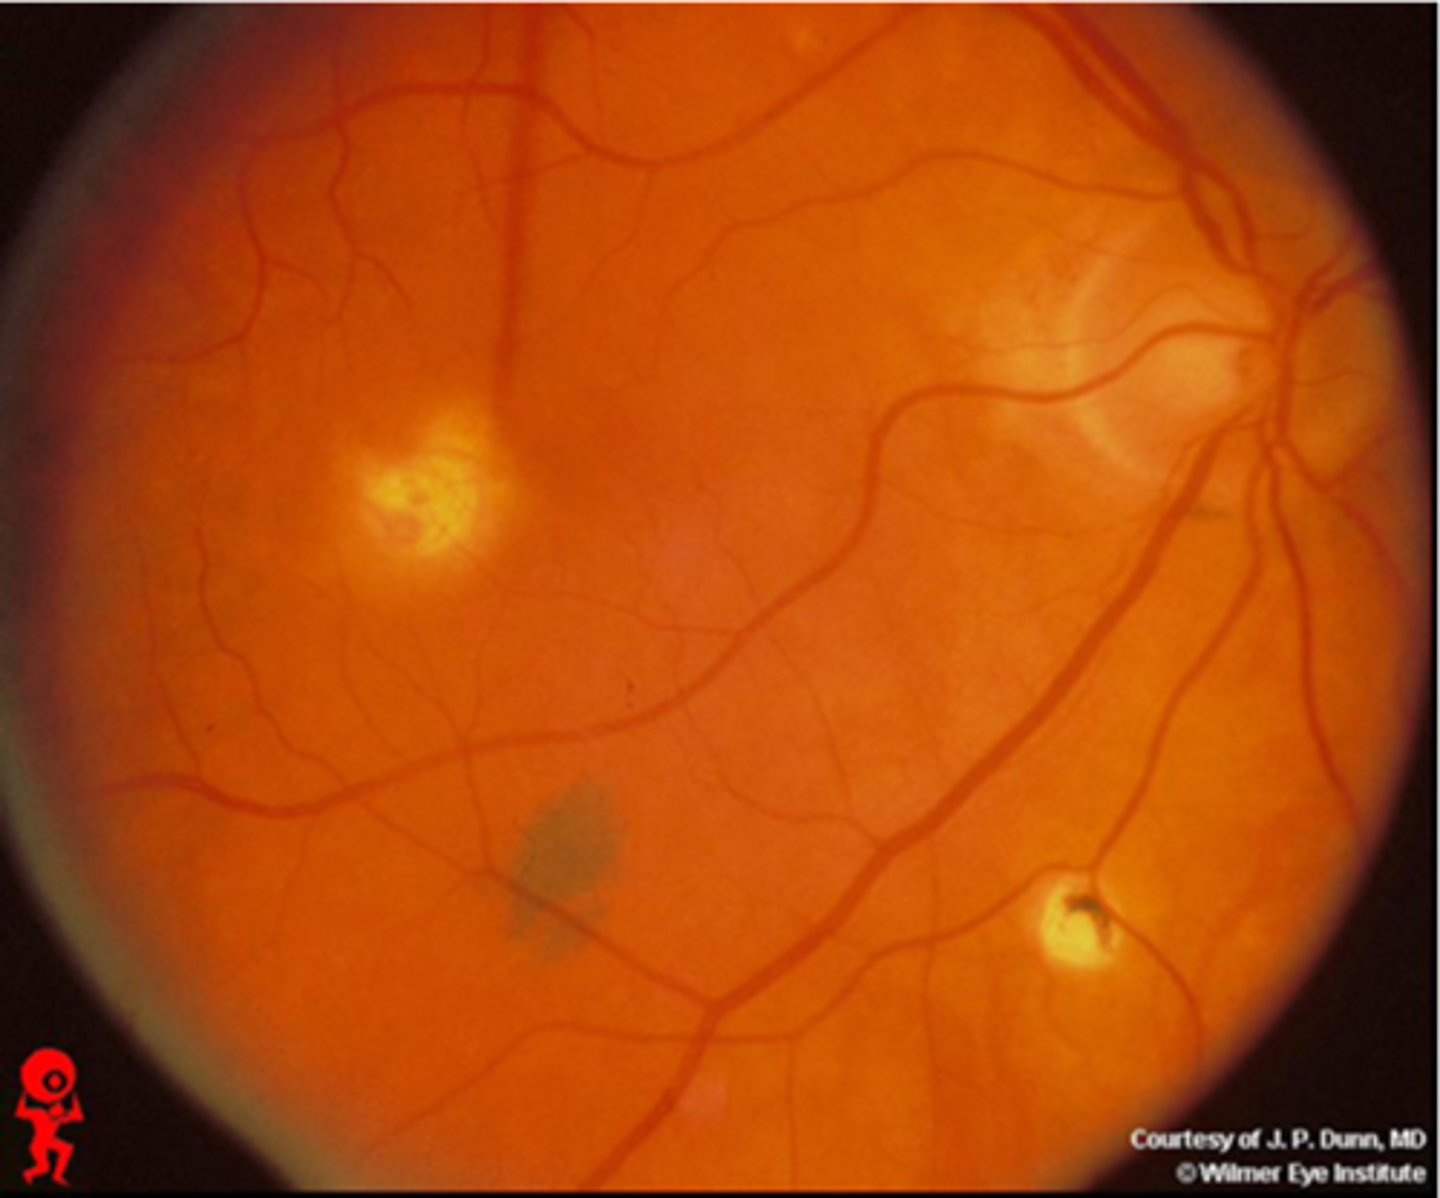

What findings of toxoplasmosis are seen here?

retinal vasculitis

exudative scar

focal, hazy vitritis and retinitis